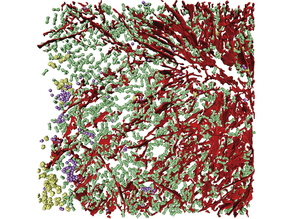

A Bloody Mess